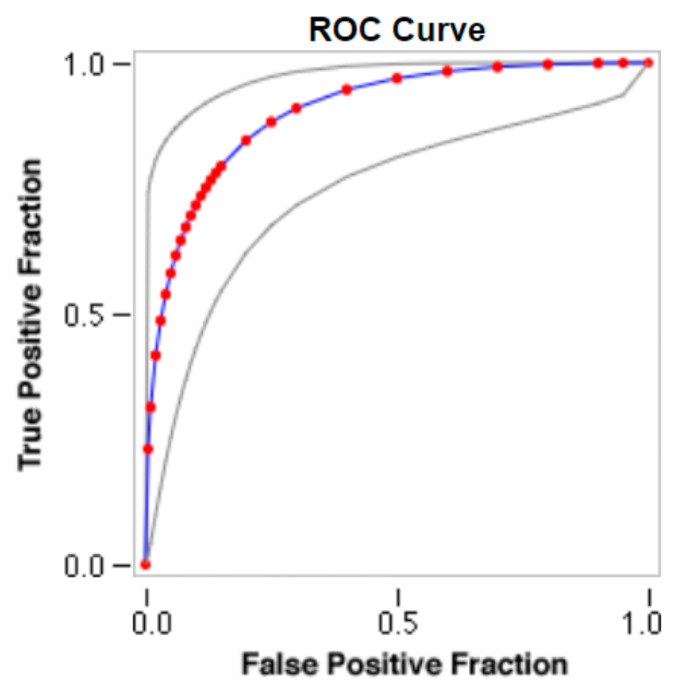

Sample images of the marginal joint space narrowing region of interest can be seen in Figure 5. The IoU (Intersection of Union) metrics were used to evaluate our region of interest detection system. This metric was the size of the intersection between the area of the actual bounding box and the area of the predicted bounding box divided by the size of the area of both boxes added together. When the IoU was 0.70, the narrow marginal joint space was found in 99.72% of the knee joints using our presented model. Additionally, Figure 6 depicts the ROC curve for marginal joint space narrow detection. The results of the presented marginal joint space narrow detection model obtained a sensitivity rate of 98.67%, a Dice score of 98.58%, a precision rate of 98.46%, a specificity rate of 98.50%, a false positive rate of 0.0100, a false negative rate of 0.0197, and an overall accuracy rate of 98.97%, as shown in Table 6, and the graphical illustration of Table 6 values is depicted in Figure 7. Table 7 demonstrates the metric performance outcomes of the proposed ResNet101 and VGG16 model to classify the RA. From Table 7, the outcome of the VGG16 outperforms the well-pre-trained ResNet101 model in classifying RA.